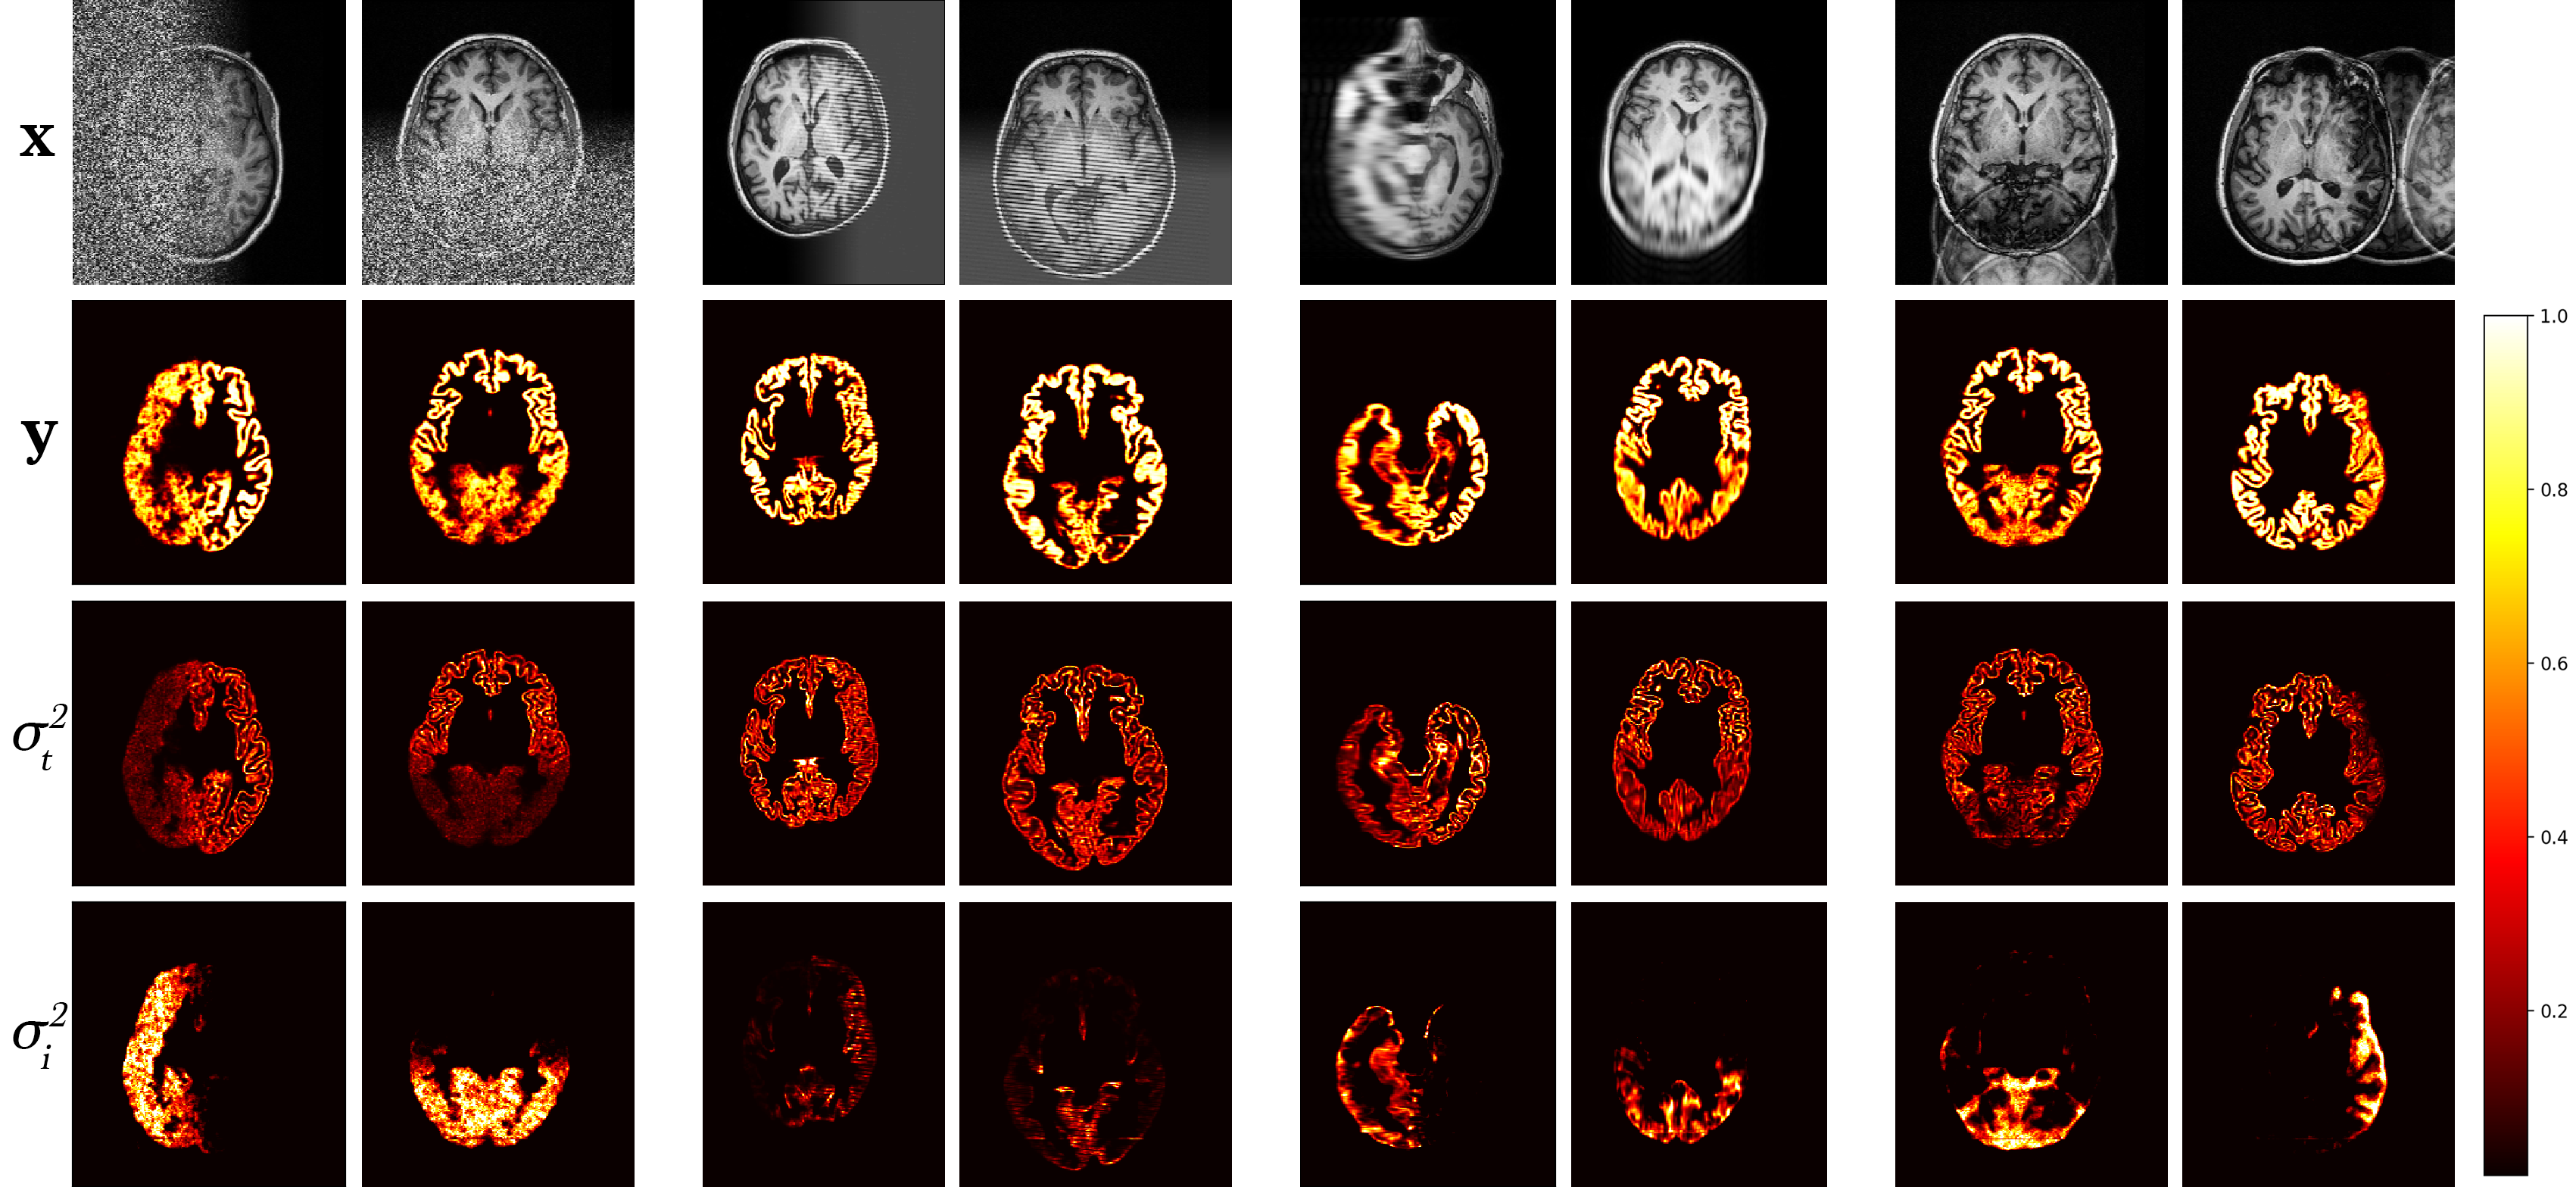

A model trained with artefact augmentation was used to perform inference on the hold-out test set. Figure 4 presents a selection of qualitative results. For each image sample, predicted segmentation, task and corresponding augmentation uncertainties are displayed. Areas of high uncertainty are generally in the artefacted regions. This enables us to quickly locate in the volume the image quality issue and judge its effect on the prediction by the level of uncertainty. Note, that in cases of heavy noise, the task uncertainty decreases as the signal is impaired, and therefore the model reverts back to the prior distribution.

![]() |

| (a) | (b) | (c) |

The model was trained using the clean ADNI dataset as before, with simulated k-space artefact augmentation applied during training. A test set of artefacts was created using the 10% hold-out set and simulating k-space artefacts for each unique subject in all 5 artefact sub-type categories described in section 5, resulting in 140 artefact scans. Each artefact scan was generated randomly, thus creating a varied dataset with a range of image degradation severity. These artefacts were combined with the clean test images to produce the final test set. Inference was performed on the test set, producing 3D segmentation predictions , task uncertainty estimates , and 5 artefact uncertainty estimates for each of the artefact sub-types . The decoupled artefact uncertainty maps were summed to produce the total artefact uncertainty decoupled from the task, and the mean variance over the image volume was computed as our metric of segmentation quality. A sample of these results are shown in Figure 6.